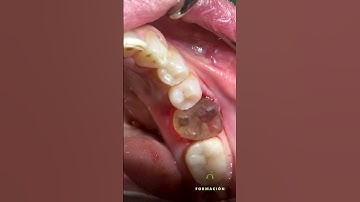

Auto-Transplantation of 28 to Replace 27 - Dr Nyer Firdoose C S